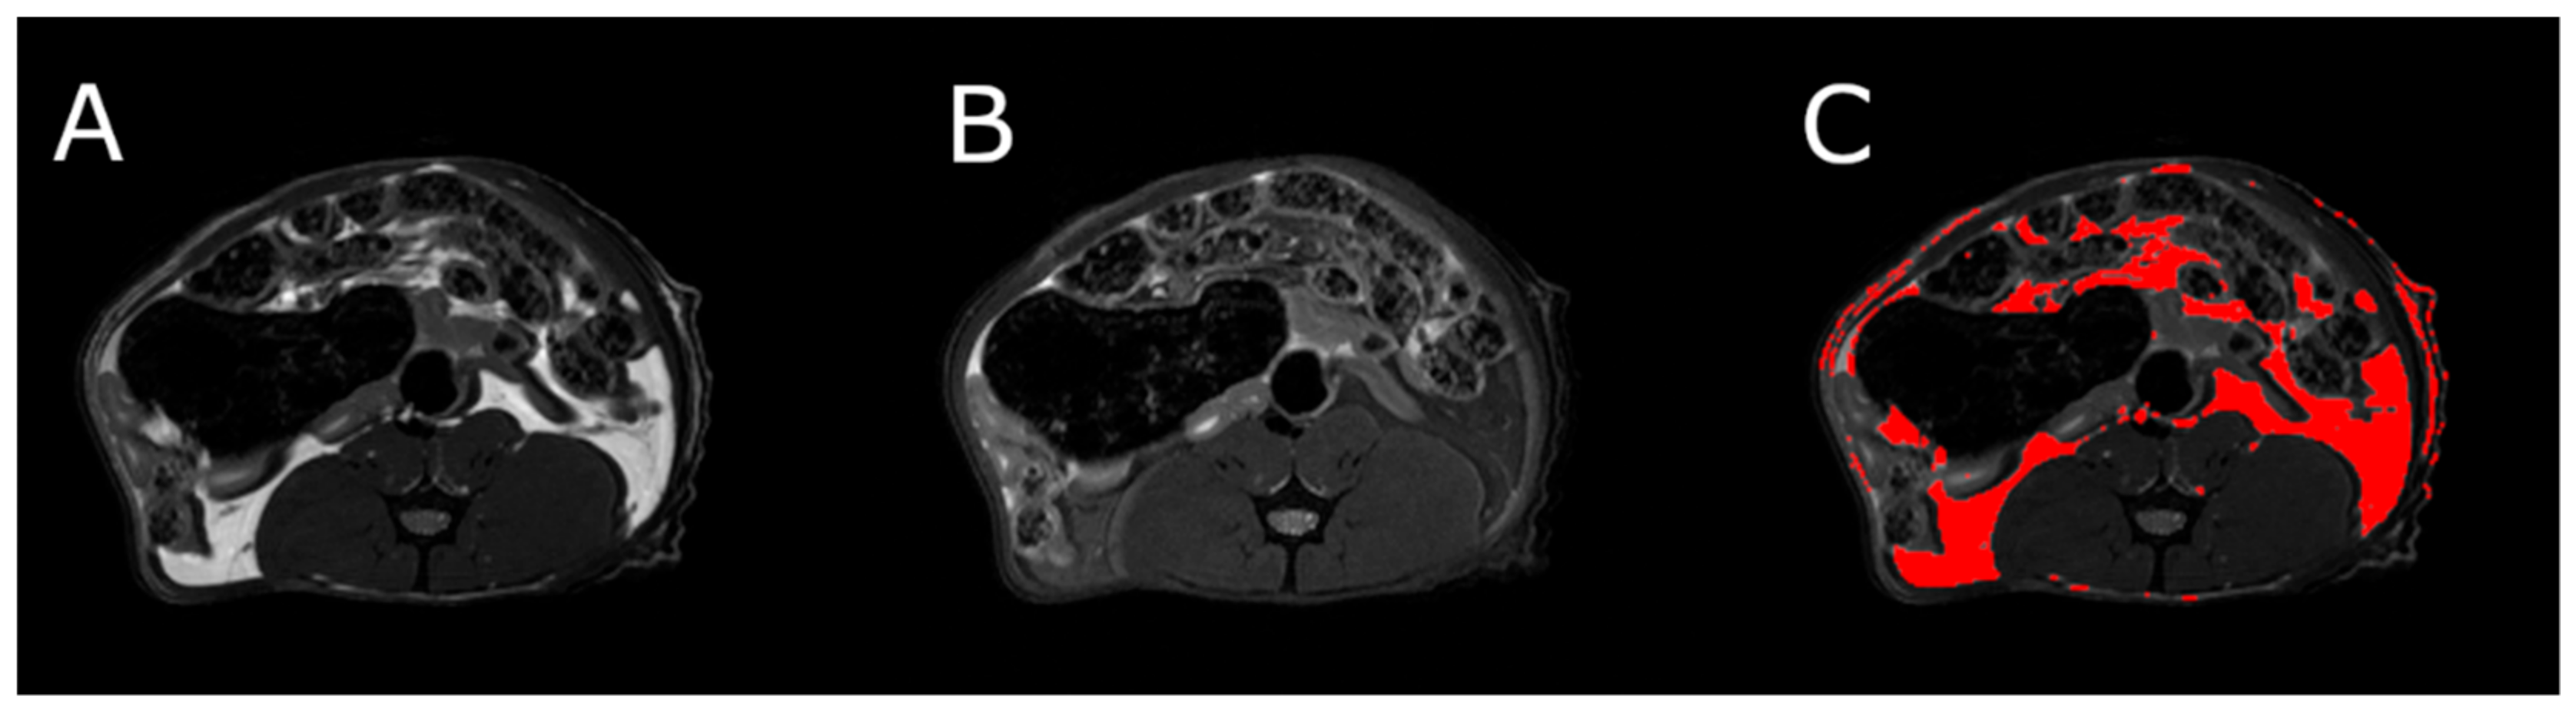

3.5. Body Composition

MRI measurements showed a significant reduction in the adipose tissue volume of ABA rats compared with controls (Figure 5). The mean visceral body fat reduction in the ABA rats reached 58.9% on day 6 of the experiment (Figure 6).

Figure 6.

MRI scan of female ABA rat, the cross section of the abdomen at L4 level. (A) RARE image without fat suppression; (B) fsupRARE image with fat suppression; (C) segmentation result—adipose tissue marked in red.